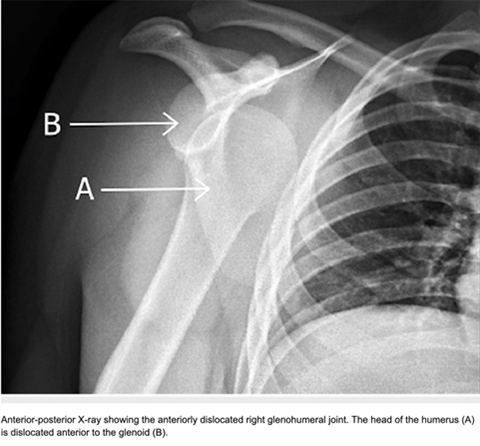

Anterior shoulder instability (ASI) is a prevalent issue, particularly among young and active individuals, often necessitating surgical intervention to restore stability and function. A recent study published in the Arthroscopy, Sports Medicine, and Rehabilitation Journal by Dr. Kelechi Okoroha and colleagues employ advanced unsupervised machine learning techniques to categorize and characterize the "optimal observed outcome" following surgical treatment for anterior shoulder instability (ASI). By analyzing data from patients under 40, it distinguishes between favorable and suboptimal postoperative outcomes and identifies demographic, clinical, and treatment variables that predict these outcomes. Using statistical analyses, including descriptive statistics and Kaplan-Meier survival curves, the goal is to enhance understanding of factors contributing to successful surgical outcomes and refine criteria for optimal results in ASI patients.